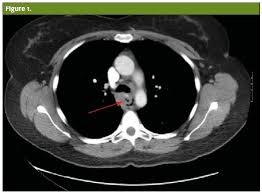

Boerhaave Syndrome Radiology Case Radiopaedia Org

Boerhaave Syndrome Radiology Case Radiopaedia Org from prod-images-static.radiopaedia.org